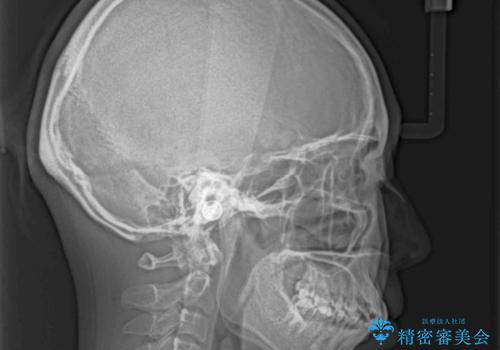

ふっくらとした口元を改善したい 目立たないワイヤー装置による抜歯矯正

- 前歯のデコボコを気にして来院された患者様です。

当初は口元の突出感はあまり気にされていない様子だったので、インビザラインによる非抜歯矯正をお勧めしたが、ふっくらとした口元を改善したいとのことで、積極的に口元の突出感を改善することとしました。

上下左右第一小臼歯4本の抜歯を行い、ワイヤー装置による矯正治療を行うこととしました。

元々上下正中の位置はずれていましたが、治療中によりズレが大きくなったので、元の位置に戻すため治療期間を余計に要しました。

横顔の印象が大きく改善され、患者様には大変満足していただきました。